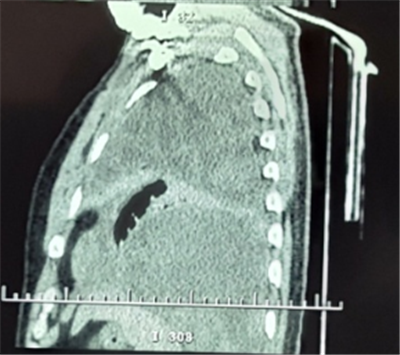

患者劉某,男性,52歲。因“胸悶、胸痛1月,發(fā)熱10余天”,就診于當(dāng)?shù)乜h醫(yī)院CT提示左側(cè)胸腔大量積液,予胸腔閉式引流同時(shí)抗感染治療,效果不佳遂轉(zhuǎn)入我院胸外科。復(fù)查胸部CT提示胸腔腫瘤合并胸腔積液。

入院后經(jīng)胸外科全體醫(yī)師對(duì)患者病情進(jìn)行綜合分析、積極術(shù)前準(zhǔn)備,于2月21日為患者實(shí)施手術(shù)治療。術(shù)中發(fā)現(xiàn)患者左側(cè)胸腔巨大腫瘤占位,體積約一個(gè)西瓜大小,幾乎完全占據(jù)了整個(gè)左側(cè)胸腔,左肺大部分被壓縮而失去功能,腫瘤與周圍組織粘連致密。切開腫物,其內(nèi)見大量魚肉樣物質(zhì)及黃色纖維素樣物質(zhì),取部分內(nèi)容物及腫物囊壁送檢冰凍切片,回示淋巴樣異型細(xì)胞。繼續(xù)游離,清除腫物內(nèi)容物,并予切除部分囊壁。

通過6小時(shí)的努力將腫瘤完全切除,出血約2000ml。術(shù)后病理檢查最終確診為胸腔尤文氏肉瘤。此種胸腔巨大腫瘤,手術(shù)難度大,術(shù)中出血多,手術(shù)風(fēng)險(xiǎn)高。